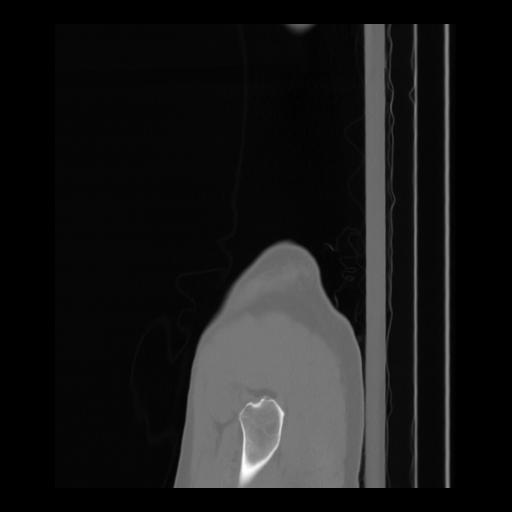

36 CUERPO,CE,Sagittal,3.000,CUERPO,Sagittal,